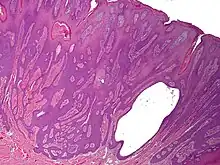

Syringofibroadenoma is a cutaneous condition characterized by a hyperkeratotic nodule or plaque involving the extremities.[1]: 668